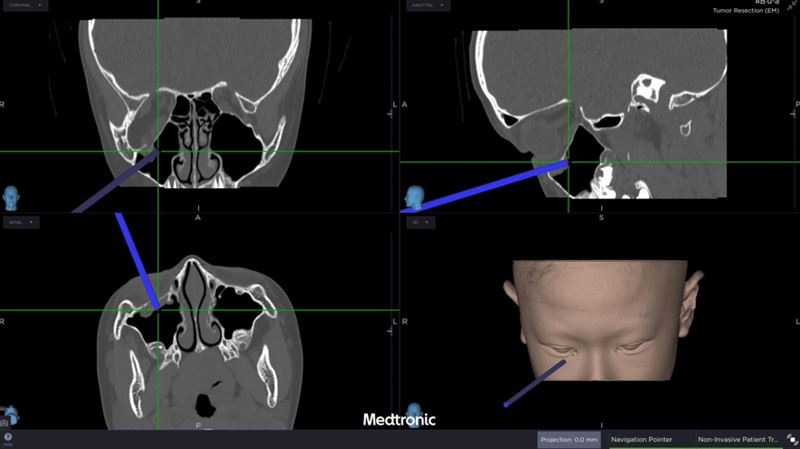

經評估後,中山醫學大學附設醫院口腔顎面外科醫療團隊邱昱瑋主治醫師、張芳語主治醫師及洪珮瑄主治醫師,立即制定手術方案,運用創新電腦數位模擬技術,術中搭配內視鏡與精密導航系統,精準定位眼底嵌頓肌肉的位置,成功將被夾住的眼底肌肉復位。術後,女童的複視症狀消失,眼球活動恢復正常,並未留下相關併發症,順利重拾日常生活與學習品質。

張芳語進一步表示,重建受損眼眶骨在臨床上挑戰重重,包括手術視野狹小、骨頭型態複雜、手術精準度要求高,以及術後疤痕與外觀重建的考量,透過精準的數位導航技術才能克服困難。洪珮瑄也表示,對於兒童患者而言,手術精準度與微創性格外重要,不僅要恢復功能,更要兼顧未來面容發育的完整性。